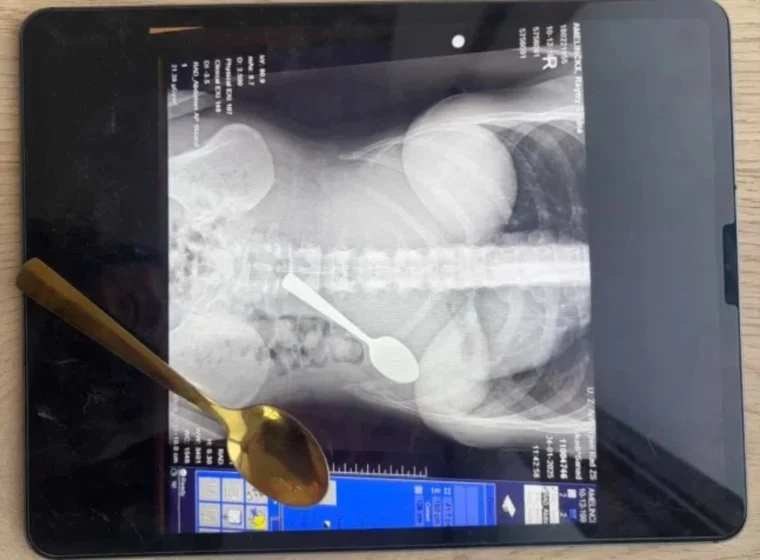

وسيطرت حالة من الذهول على الأطباء فور رؤية صور الأشعة التي كشفت عن وجود ملعقة كاملة الطول داخل معدة بشرية، وهو ما تسبب في حالة من الجدل الواسع على منصات التواصل الاجتماعي حول مخاطر التعامل مع الحيوانات أثناء تناول الطعام داخل دولة بلجيكا وباقي دول العالم.

ابتلعت ريمي أملينكس البالغة من العمر 28 عاما ملعقة معدنية بطول 17 سنتيمترا عن طريق الخطأ أثناء تناولها الزبادي داخل منزلها في دولة بلجيكا، ووقعت الحادثة الصادمة عندما قفز كلبها النشيط من نوع هنغاريان فيزلا على جسدها بشكل مفاجئ مما أدى إلى اندفاع الملعقة داخل حلقها بسرعة البرق، وحاولت ريمي أملينكس إخراج الأداة المعدنية بيدها لكنها شعرت بانزلاقها بسلاسة نحو المعدة واختارت ابتلاعها بالكامل لتجنب انسداد مجرى الهواء والاختناق المحقق، وكتمت الضحية سرها عن شريك حياتها لعدة ساعات بسبب شعورها الشديد بالحرج قبل أن تقرر التوجه إلى المستشفى بعد شعورها بآلام مبرحة وانتفاخ غير طبيعي في جسدها داخل دولة بلجيكا.

خضعت ريمي أملينكس لعملية منظار معدة عاجلة تحت التخدير الموضعي بعد أن أكد الأطباء استحالة خروج الملعقة بشكل طبيعي نظرا لطولها الفارع الذي يصل إلى 17 سنتيمترا، واضطر الفريق الطبي لتدوير الملعقة بحذر شديد داخل أحشاء المريضة لاستخراجها مما نتج عنه نزيف طفيف في المعدة والتهاب حاد في الحلق استمر لفترة طويلة، وأكدت التقارير الطبية في دولة بلجيكا أن ريمي أملينكس عانت من الغثيان وصعوبة النوم طوال يومين كاملين بسبب حركة المعدن داخل جسدها قبل التدخل الجراحي، وخرجت السيدة من المستشفى بسلام دون أضرار دائمة لكنها قررت الاحتفاظ بتلك الملعقة كتذكار غريب لتوثيق أغرب موقف تعرضت له في حياتها.